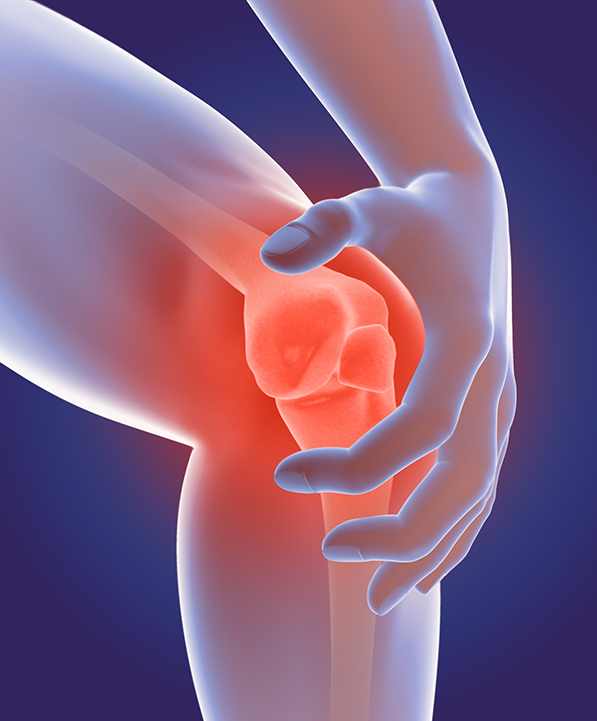

REUMATOLOGIJA

Neobično otkriće o reumatoidnom artritisu

Istraživači sa Medicinskog fakulteta Univerziteta u Virdžiniji, SAD, na neočekivan način su došli do novih nalaza o razvoju reumatoidnog artritisa. Primetili su da brisanje gena ELMO1 ublažava simptome artritisa kod miševa, što je bilo posebnoiznenađujuće zbog toga što se prvobitno smatralo da gubitak ELMO1 dovodi do povećane upale.